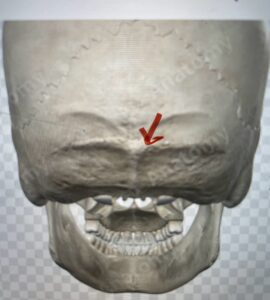

Although some patients do not require a decompression and just require an occipital cervical fusion, most require some sort of decompression of the neural elements. After a decompression an instrumented fusion is performed. A useful anatomic structure for anchoring the top portion of the construct to the skull is the midline keel of the subocciput. This structure extends from the external occipital protuberance, which corresponds to the confluence of the sagittal and transverse sinuses, to just above the foramen magnum:

(Fig. 1). This bone is quite thick, about 15 mm (Figs. 2a and b). Most modern plate systems utilize three midline keel screws with the option to place within a 2 cm lateral fixation point. This plate is connected to sometimes tricky-to-bend rods and connected to screw fixation points in the cervical spine (Fig. 3). Bone graft material extends from skull to cervical spine.

Fig. 1: Diagram of occipital bone to foramen magnum. Note external occipital protuberance (red arrow)

Fig. 2a: Cartoon illustrating posterior projection of internal skull structures demonstrating the midline keel in the subocciput above the foramen magnum.